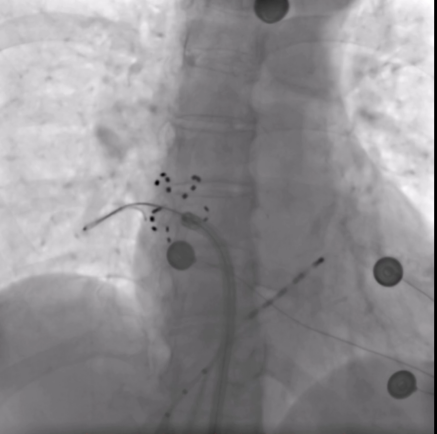

4.效果验证:术中通过起搏验证法确认四根肺静脉均实现100%电隔离,手术圆满成功。

(术中消融后对肺静脉进行双向阻滞起搏验证电生理检查)